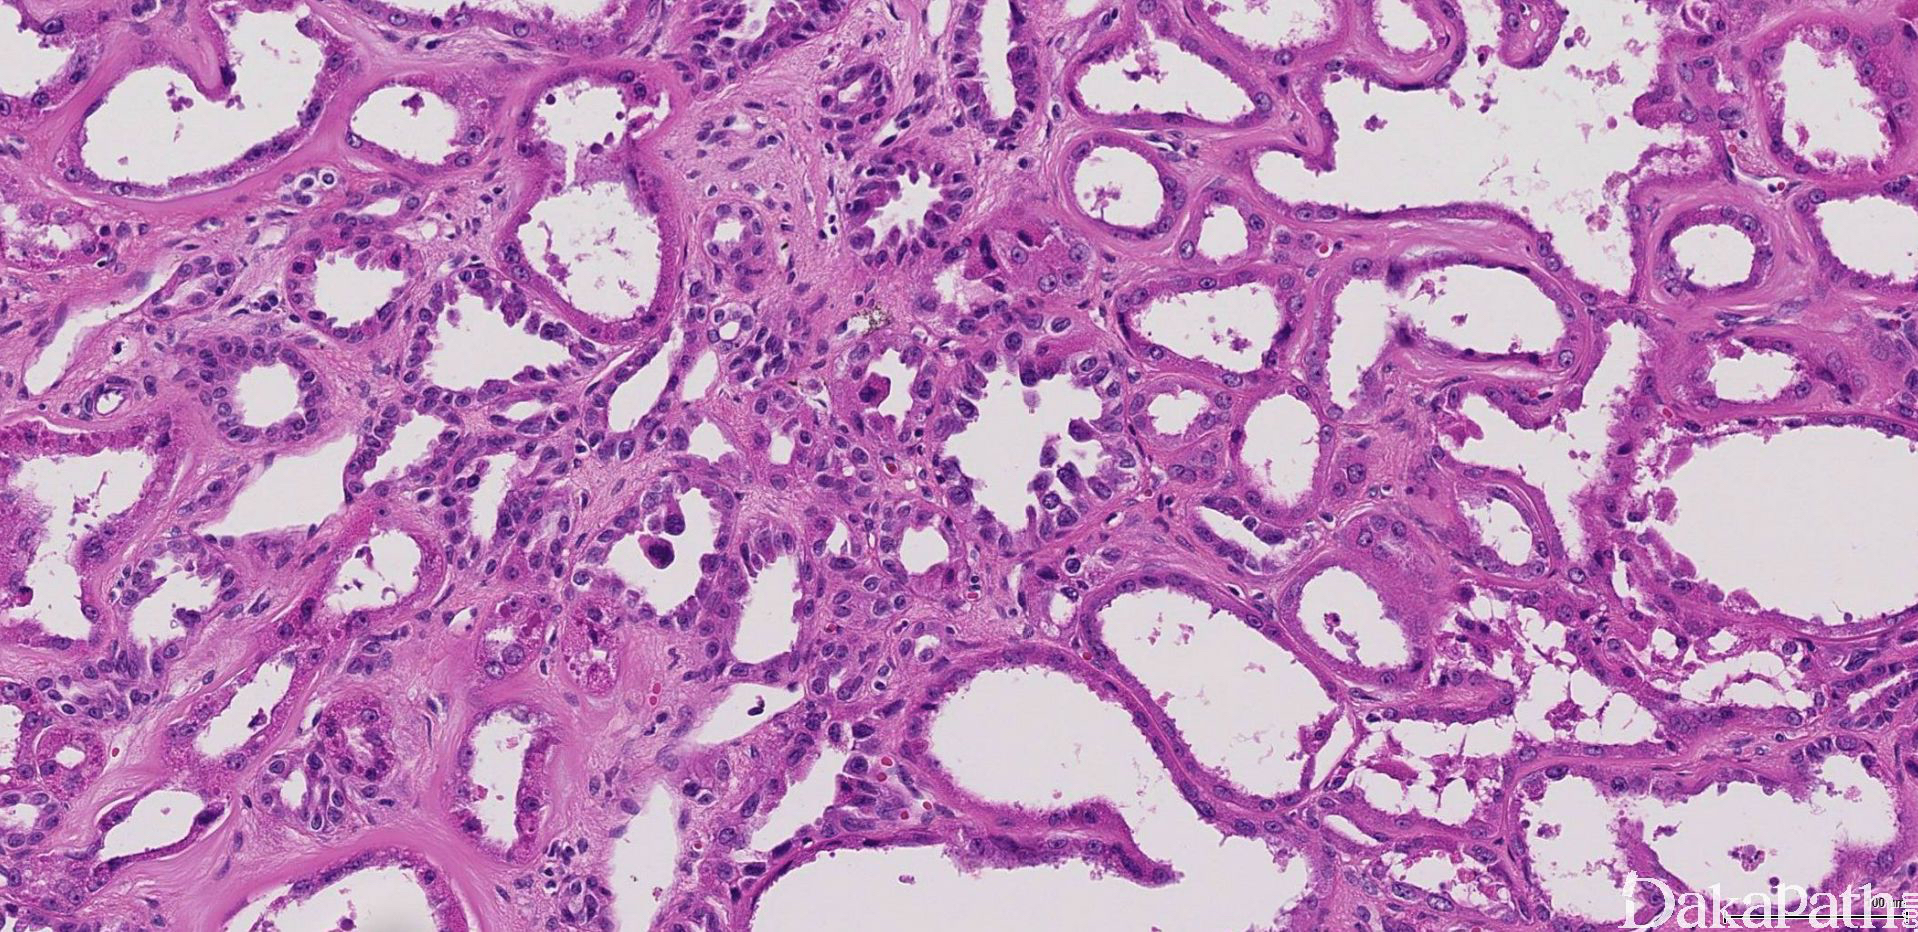

低倍镜下完全由小到中等大的小管和较大的囊肿组成(图 1);被覆瘤细胞单层排列,呈扁平、立方状到柱状、鞋钉样不等(图 2)。管腔或囊腔内容物空,有时可见浅染的嗜酸性分泌物或出血。

瘤细胞胞浆丰富嗜酸性,核圆形或不规则,常见较明显的核仁(ISUP 核分级:3 级,图 3)。

小管或囊肿之间为薄壁的少细胞纤维性间质,一般无炎症浸润或水肿变性。